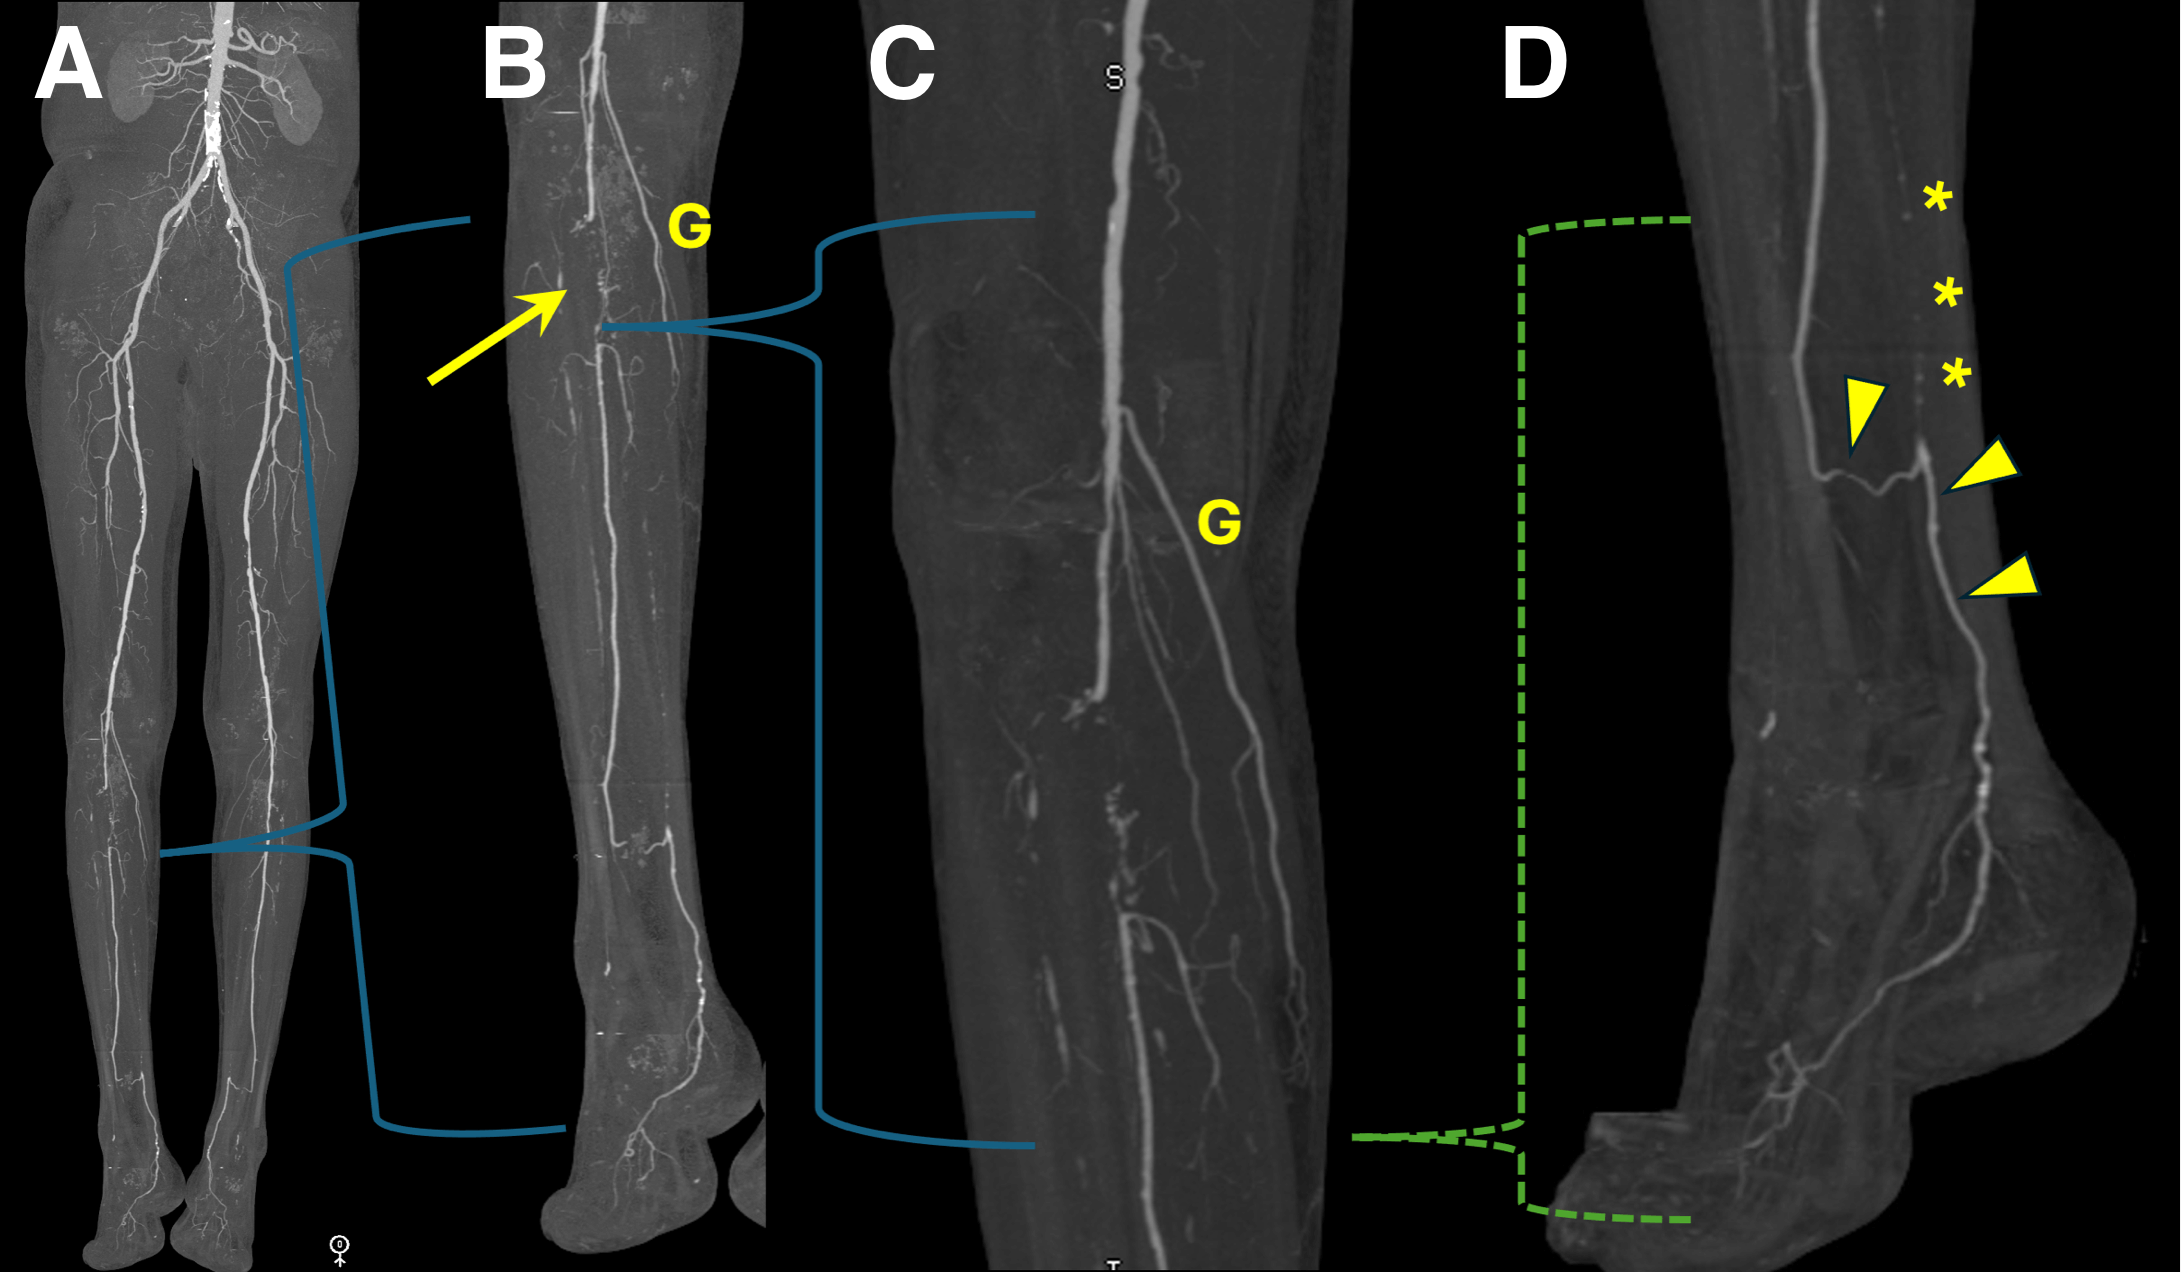

Figure A-D: Right leg.

Figure A. Overview bone-segmented maximum intensity projection (MIP) image shows no significant inflow or femoropopliteal steno-occlusive disease.

Figure B. MIP image of right calf vessels shows occlusions of both the posterior tibial and anterior tibial arteries, with segmental occlusion of the proximal peroneal artery (arrow). There is peroneal reconstitution from adjacent collaterals including geniculate vessels (G).

Figure C. Small field of view MIP image shows collateral reconstitution of the peroneal artery. G = Geniculate artery branches.

Figure D. Small field of view MIP image at the ankle shows peroneal reconstitution of the posterior tibial artery (arrowheads), which continues patent across the ankle. Proximal to the reconstitution, calcifications within the occluded posterior tibial artery can be seen (* * *).